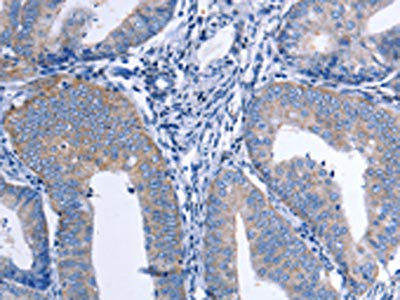

The image on the left is immunohistochemistry of paraffin-embedded Human thyroid cancer tissue using CSB-PA163077(CCL26 Antibody) at dilution 1/20, on the right is treated with synthetic peptide. (Original magnification: ×200)

The image on the left is immunohistochemistry of paraffin-embedded Human cervical cancer tissue using CSB-PA163077(CCL26 Antibody) at dilution 1/20, on the right is treated with synthetic peptide. (Original magnification: ×200)